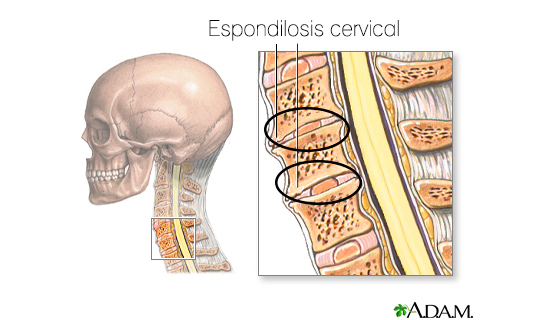

Espondilosis cervical

Este trastorno se caracteriza por dolor intermitente o de manera crónica en el cuello y dolor o rigidez en el hombro, dolores en la cabeza, mano y brazo, entumecimiento, hormigueo, y sentimiento de torpeza en los movimientos. Entre las causas está incluida la degeneración del disco vertebral por la edad, que conduce a los nervios la compresión y el daño de la médula espinal, artritis, además del tiempo dedicado con el cuello en posturas incómodas.